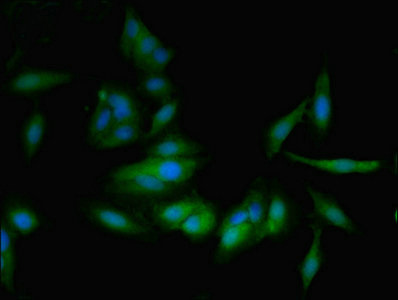

應(yīng)用范圍:ELISA, IHC, IF

Application Recommended Dilution IHC 1:20-1:200 IF 1:50-1:200 -